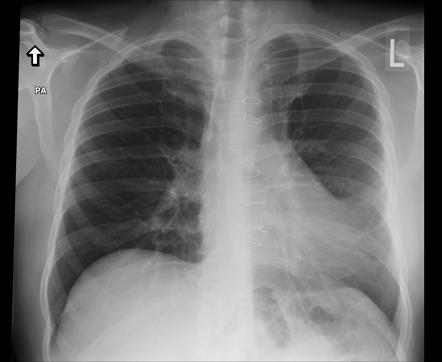

LearningRadiology - Poland, Syndrome

learningradiology.comsyndrome poland learningradiology here arrows left muscle same without click

Poland Syndrome | Image | Radiopaedia.org

radiopaedia.orgLiving With Poland Syndrome. How To Live With Poland Syndrome?

radiopaedia.orgLiving With Poland Syndrome. How To Live With Poland Syndrome?

Poland Syndrome – Radiology Cases

radiologycases.myPoland Syndrome - Stock Image - C021/1675 - Science Photo Library

radiologycases.myPoland Syndrome - Stock Image - C021/1675 - Science Photo Library

Poland Syndrome | Radiology Case | Radiopaedia.org

radiopaedia.orgPoland Syndrome Causes, Symptoms, Diagnosis, Treatment & Prognosis

radiopaedia.orgPoland Syndrome Causes, Symptoms, Diagnosis, Treatment & Prognosis

Poland Syndrome – Radiology Cases

radiologycases.myWhat Is Poland Syndrome And How To Treat It? – Healthy Food Near Me

radiologycases.myWhat Is Poland Syndrome And How To Treat It? – Healthy Food Near Me

healthy-food-near-me.comPoland Syndrome – Radiology Cases

healthy-food-near-me.comPoland Syndrome – Radiology Cases

Poland Syndrome | Radiology Reference Article | Radiopaedia.org

radiopaedia.orgsyndrome radiopaedia radiology

radiopaedia.orgsyndrome radiopaedia radiology

Poland Syndrome | Radiology Reference Article | Radiopaedia.org